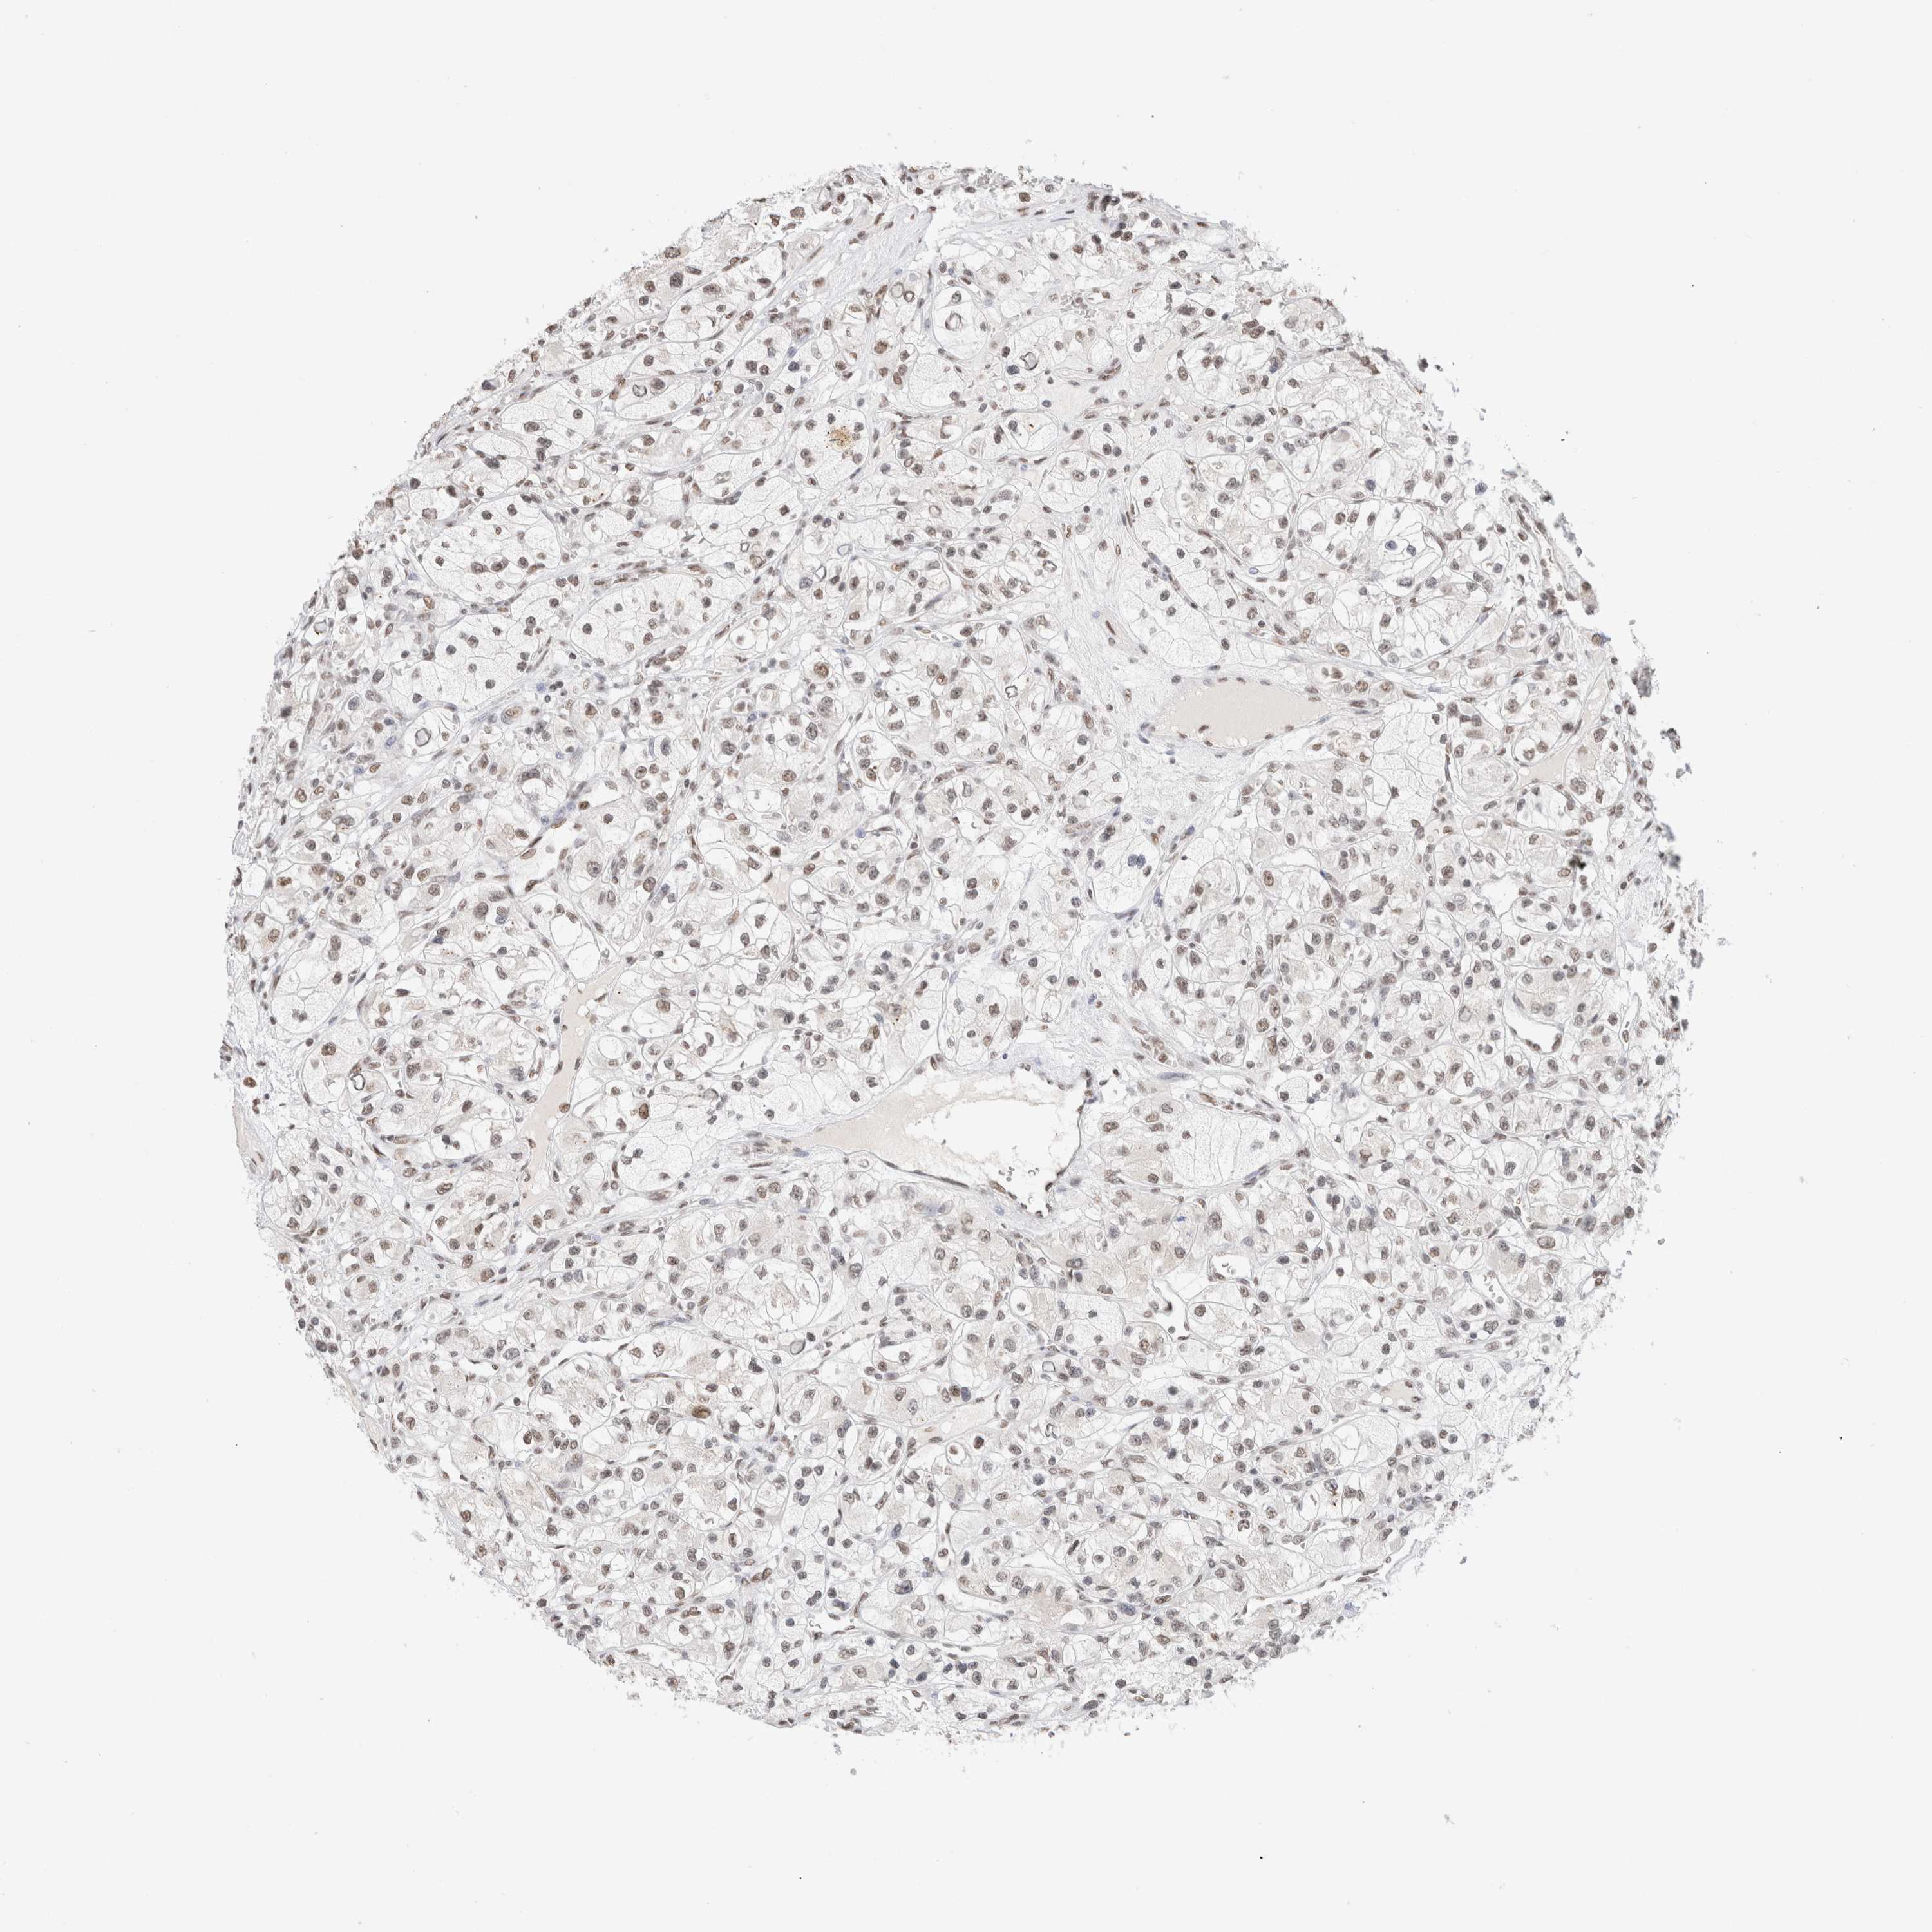

KIDNEY RENAL CLEAR CELL CARCINOMA (VALIDATION) - Interactive survival scatter ploti

SUPT3H is not prognostic in Kidney Renal Clear Cell Carcinoma (validation)

: 3.35

Average pTPM 3.9

Number of samples 100